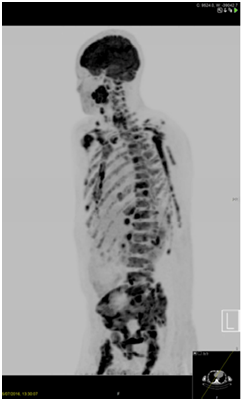

A whole-body PET-CT scan was performed. This revealed FDG avidity on the left side of the neck with further abnormal foci noted within the left tonsillar bed, lateral left side of the tongue base and lower cervical node chain (Figure 2). It also showed tracer uptake of the skull vault, skull base, mandible, all of the vertebral bodies, both humeri, both scapulae, multiple ribs, sternum, pelvis and both proximal femora. At these sites there was evidence of mixed lytic and sclerotic disease. No encroachment of the spinal cord was seen. Three small FDG avid intrahepatic lesions were also noted and there was a small FDG avid lower right-sided para-aortic node also (Figure 3). Spleen, kidneys, adrenals, bowel and prostate were noted to be normal. Laboratory panel showed a haemoglobin of 81g/dL, white cell count of 7.2, platelets of 5 and an LDH of 1057. Other markers, including calcium, were within the normal range. A blood film showed a leucoerythroblastic picture with normocytic, normochromic red cells, some polychromatic cells, thrombocytopaenia, a left neutrophil shift, myelocytes and occasional blast cells. Lymphocytes were small and mature.

Figure 2 18FDG PET confirming the head and neck primary plus multiple spinal, Sternal, Pelvic, Humeral and Extra-osseous metastases (including liver).